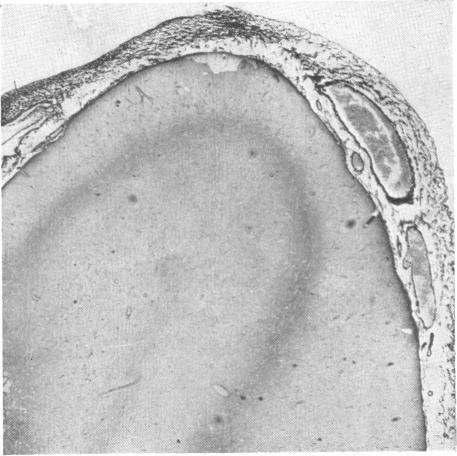

A case of renal failure and osteosclerosis.

Br Med J. 1962 Sep 22;2(5307):769-71. doi: 10.1136/bmj.2.5307.769.